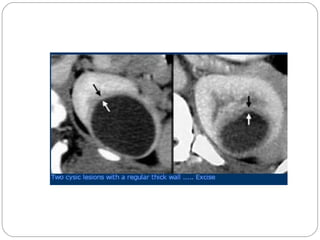

CATEGORY III

 Indeterminate cystic masses

 Thick, irregular calcification in walls or septa

 Irregular borders

 Thickened or enhancing septa

 Uniform wall thickening or that contain small non enhancing nodules

 Examples –

multilocular cystic nephroma

lymphangioma

hydatid cyst

cystic renal cell carcinoma